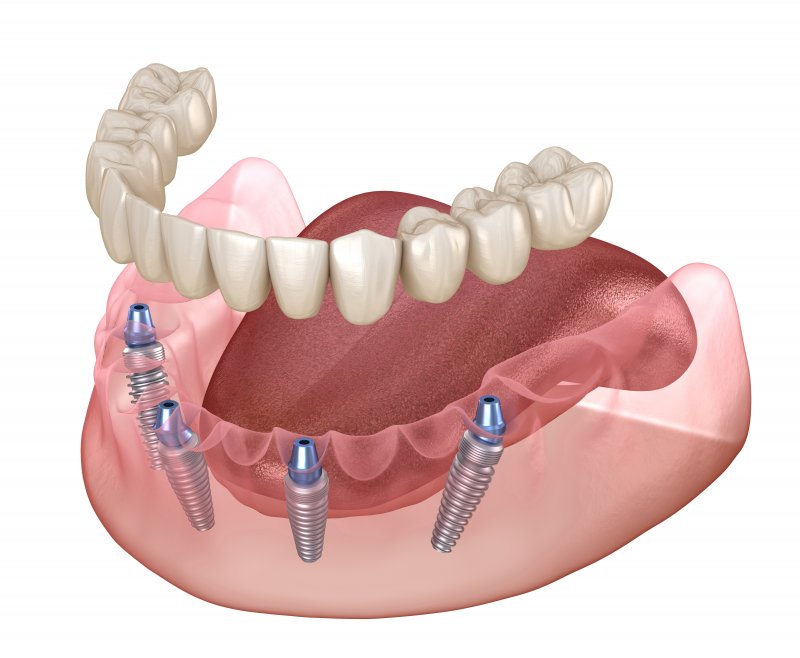

Traditional dentures are designed to hold their place in the mouth through natural suction, and they restore only about 20% of the patient’s original chewing power and must be replaced every few years. All-on-4 dental implants, on the other hand, allow a permanent restoration that offers superior chewing power to be mounted on only four implants, which minimizes how much surgery the patient will have to undergo. While many implant dentures are designed to remain fixed in the mouth, some all-on-4 dentures are designed to be removed for hygiene purposes.

All-on-4 implants are designed to be placed when minimal jawbone structure is present, so patients will rarely need to receive bone grafts to qualify for them. In many cases, the rearmost implants are positioned at angles that allow them to maximize how much contact they make with the jawbone, which sets them up for extra stability.